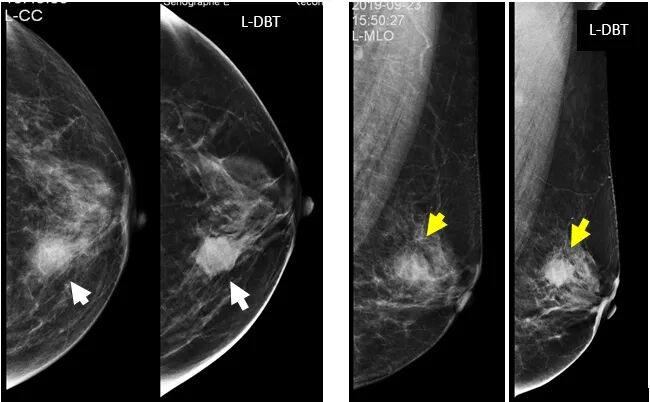

病例7:CC,MLO/DBT显示:肿块伴结构扭曲,周围毛刺及扭曲结构显示显著优于MG。病理:浸润性导管癌

4.不对称性致密影的显示

病例7:查体:未扪及肿块,腺体中R-2D-CC卵圆形不对称致密,DBT显示球形不对称为乳腺正常腺体结构。

通过对比我们明显看出传统乳腺摄影由于周围致密的腺体组织重叠影响,很难辨认肿块的边界及形态,特别在致密型腺体的病人中乳腺癌的漏诊率高达76%。而在DBT影像中,可以很清楚的显示肿块的位置和形态,大大提高了乳腺癌的检出率,降低了漏诊率,特别是对某些不可触及的早期乳腺癌的诊断,具有十分重要的意义。